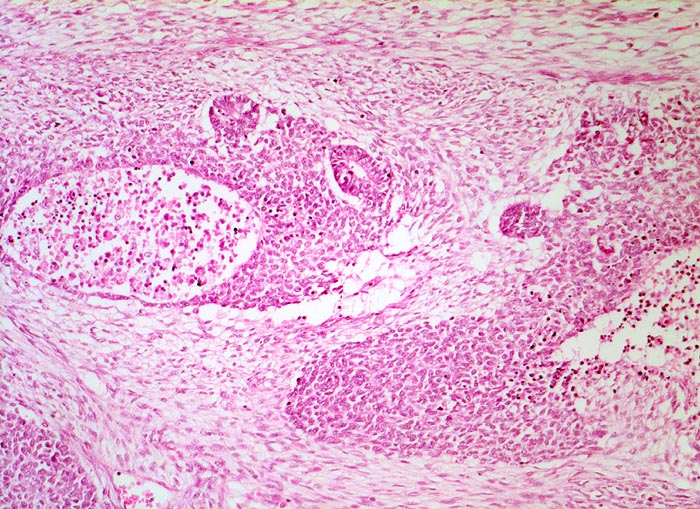

Wilms-Tumor

Beschreibung

Alle drei Komponenten des Wilms Tumors sind auf diesem Bild sichtbar. Das lockere spindelzellige Stroma, die zelldichte Blastemkomponente mit Nekrosen und Einschluss epithelialer Elemente in Form von Tubuli.

Graubrauner scharf begrenzter weicher Tumor mit fokalen Nekrosen und Einblutungen.

Palpabler Tumor im linken Hemiabdomen. Makrohämaturieepisode.

Histologie

50